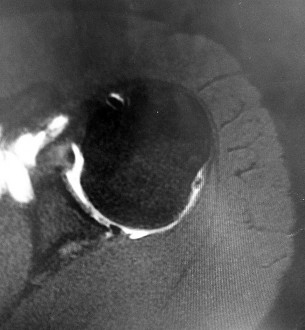

Question 5:

A 13-year-old obese boy presents with 3 weeks of left groin pain and a limp. Examination reveals obligatory external rotation of the left hip during passive flexion. A radiograph is provided. What is the recommended definitive management for a stable slipped capital femoral epiphysis (SCFE)?

Correct Answer: In situ single screw fixation

Explanation:

A stable SCFE is characterized by the patient's ability to bear weight (with or without crutches). The standard of care for a stable SCFE is in situ fixation with a single cannulated screw placed centrally within the epiphysis. Closed reduction is contraindicated due to the high risk of avascular necrosis.